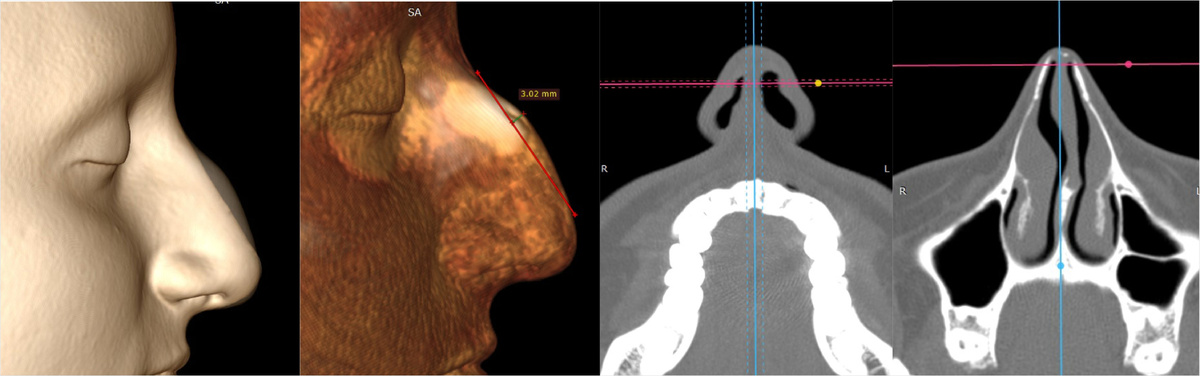

Во время консультации с помощью КТ носа и околоносовых пазух удалось установить объективные причины нарушения дыхания. Визуально были обнаружены деформированные участки перегородки носа.

С применением 3D-реконструкции лица пациентки и наложением мягкотканевых структур, были проанализированы анатомические причины измененной формы носа. Пациентке были предложены различные варианты моделирования, из которых она выбрала наиболее подходящий.

Снимки КТ носа и околоносовых пазух пациентки